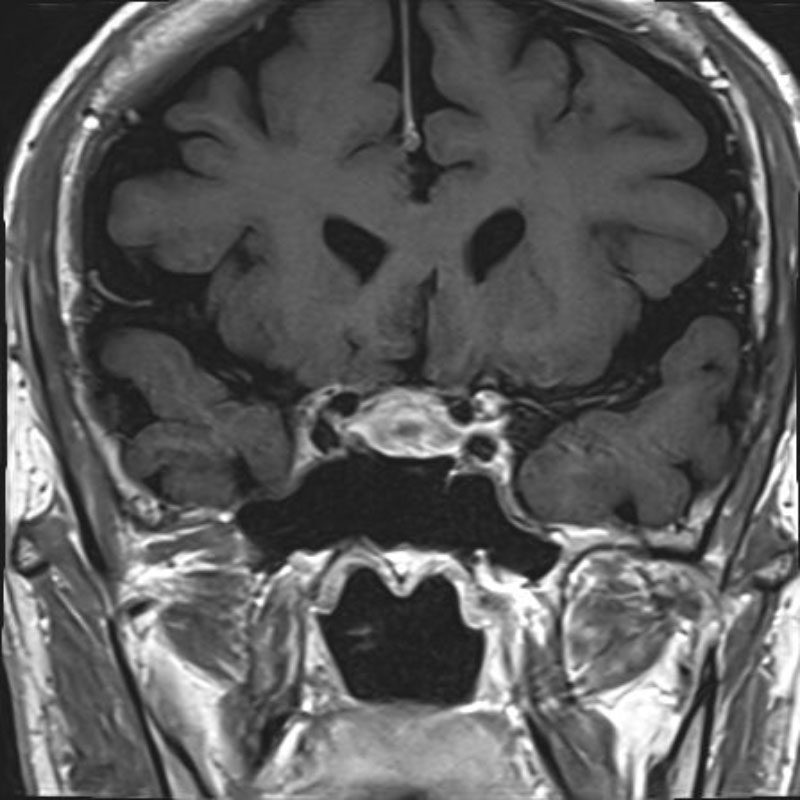

髄膜腫

頭蓋内腫瘍摘出術

No.’25_109 手術前1

No.’25_109 手術前2